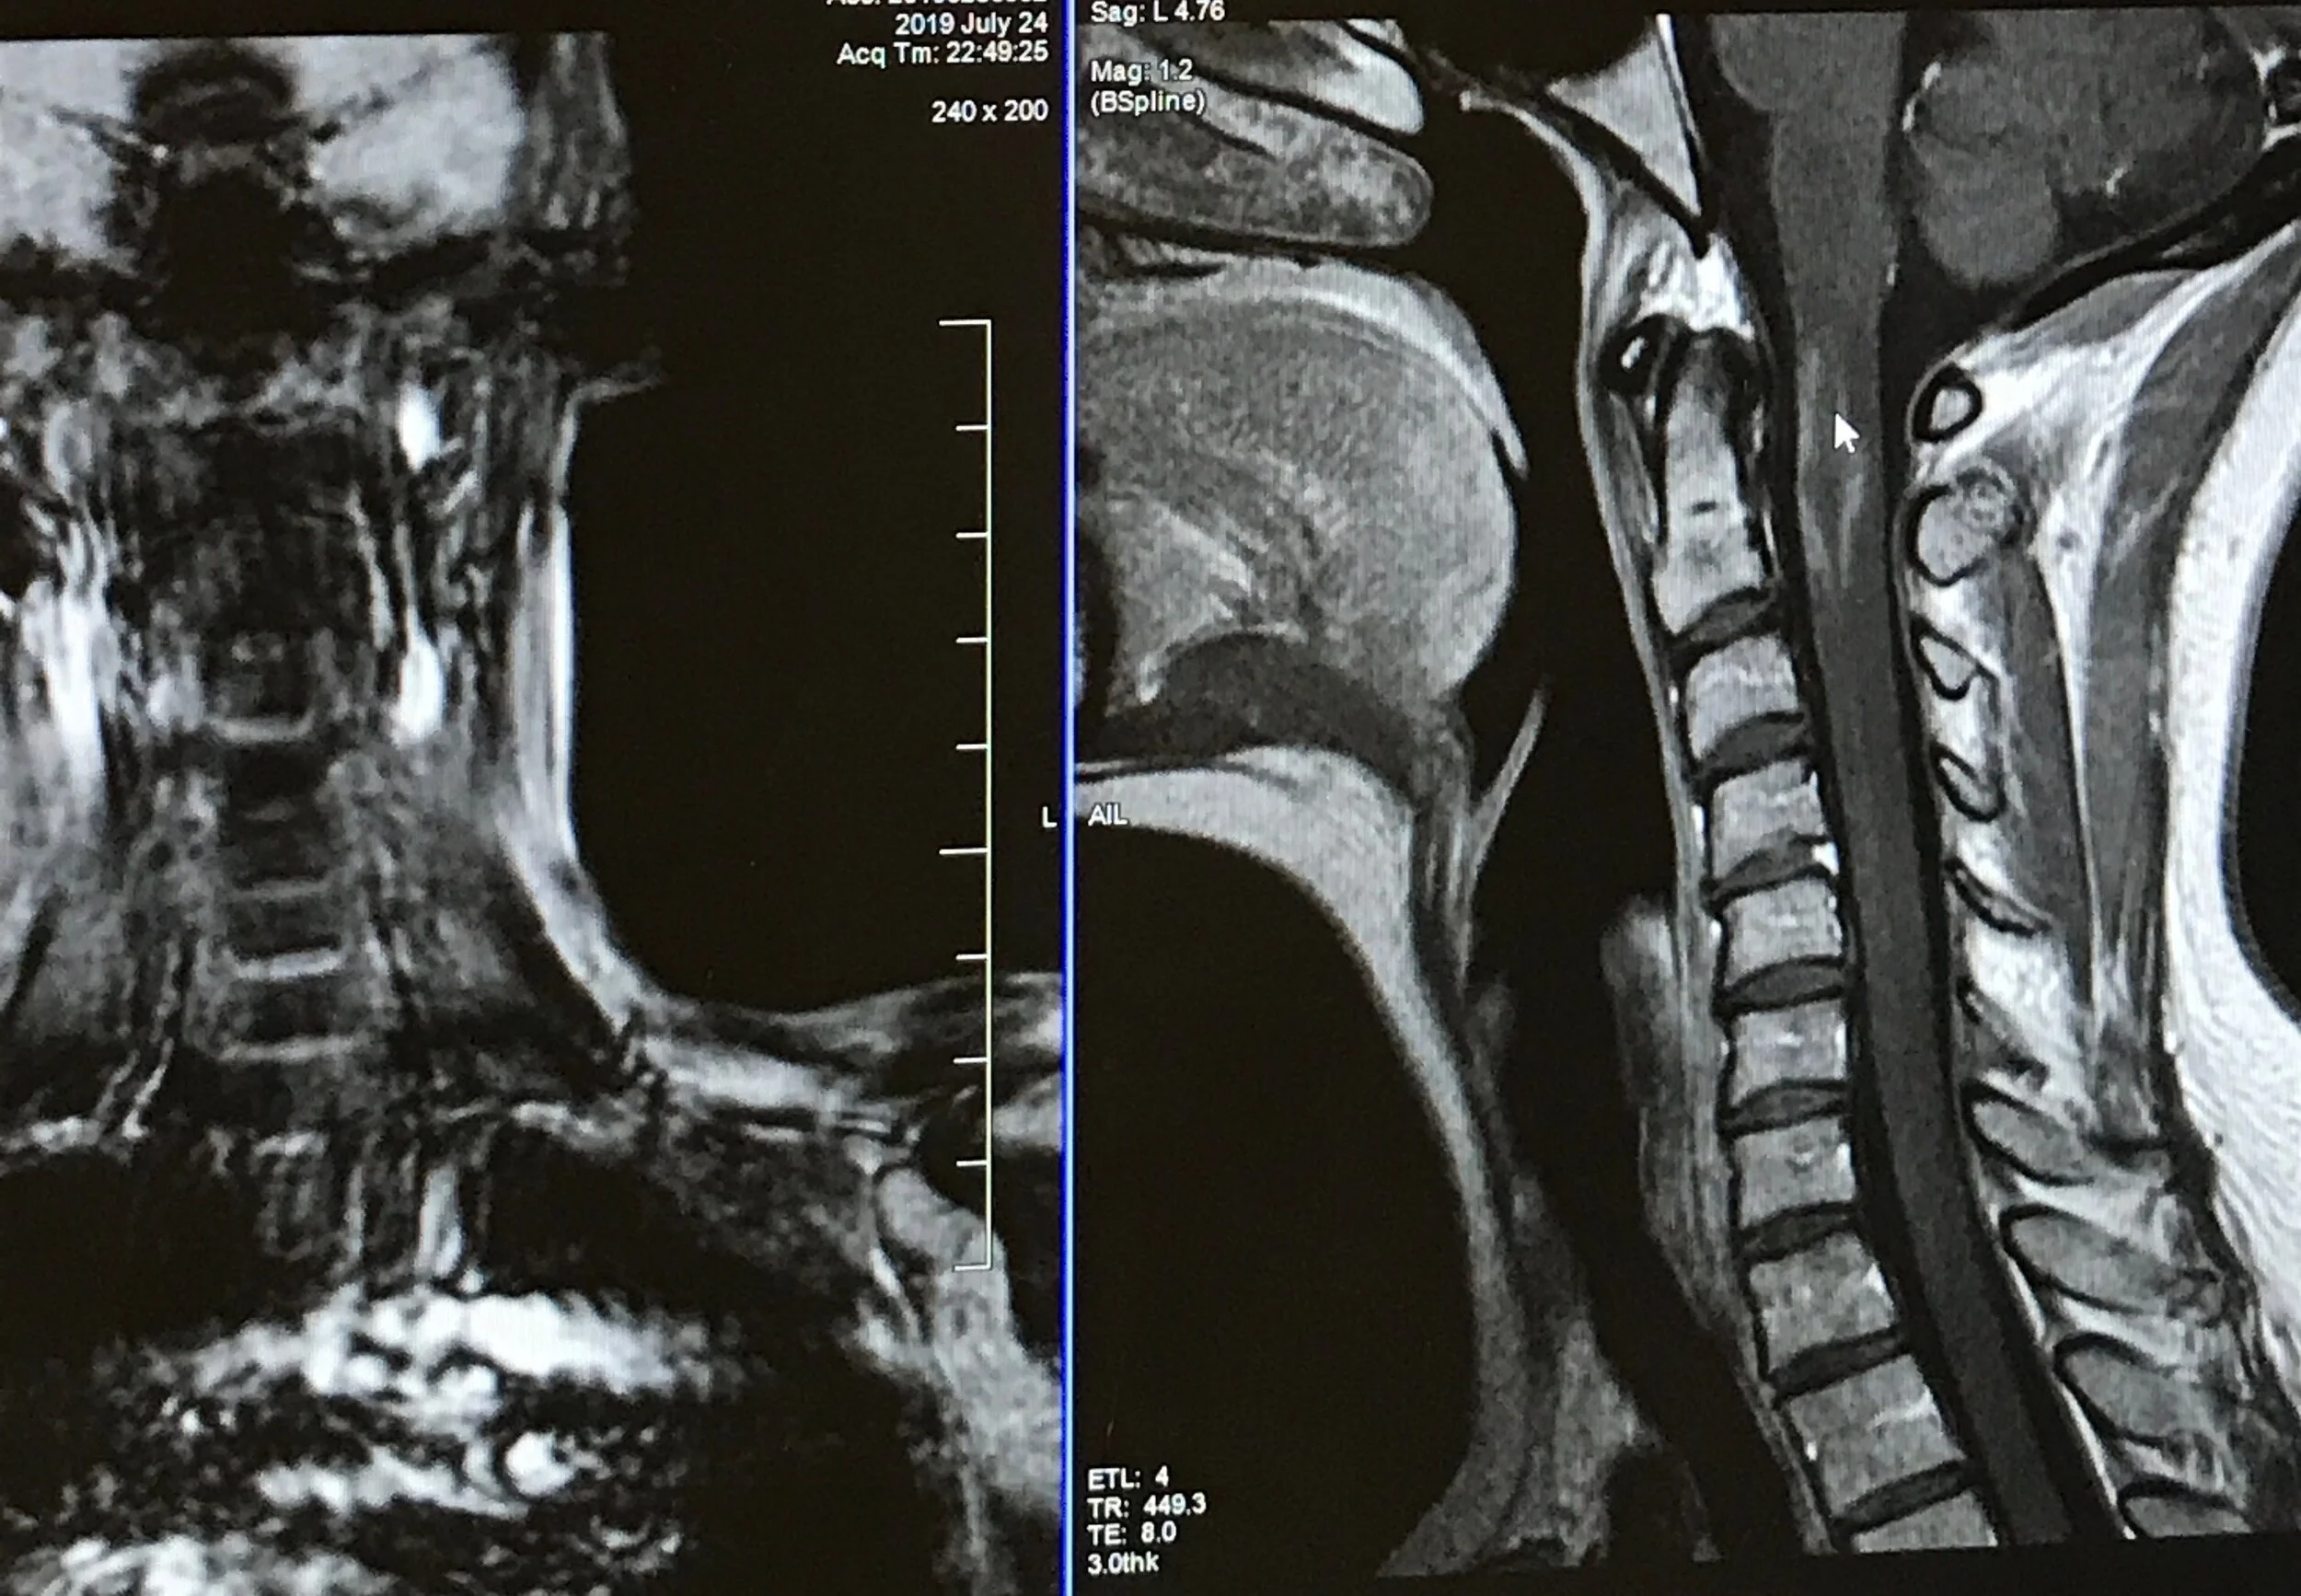

july 19 spine.jpg

July 2019 Spine

The area of concern was the angular and oval shaped area in my spinal cord, near the mouse arrow and C1 vertebrae. My neurologist said it was a fairly large lesion for how few symptoms I was having.